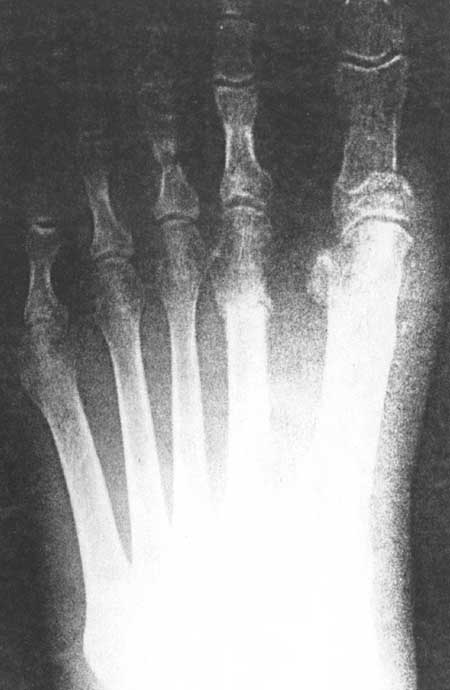

Fig 3A. (pre-operative)

|

Fig 3A (post-operative)